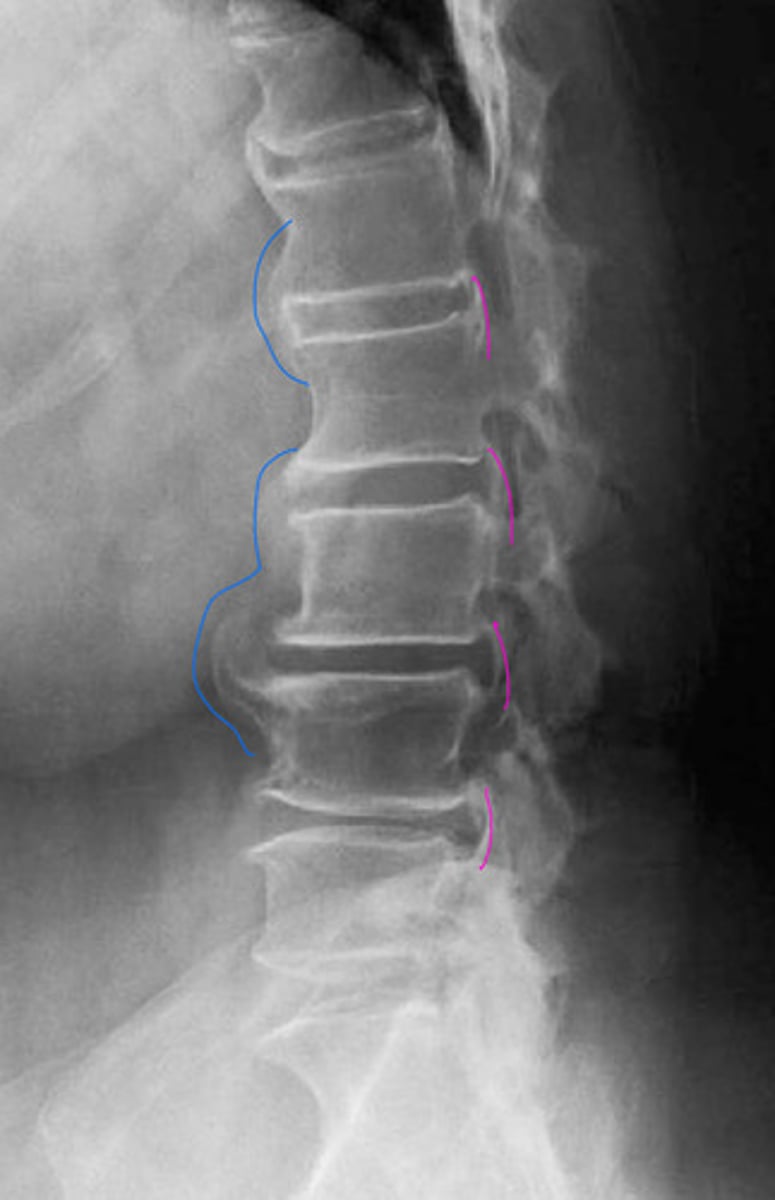

Calcification of the posterior vertebral line

Looks like fracture, not actually

What is the blue?

What is the red?

DISH

What is the blue arrow pointing at?

Sclerosis of the posterior vertebral line

What is the pink?

DISH (mid body to mid body)

What is in the red?

DISH (mid body flow of the anterior vertebral line)

What is wrong with this image?

Calcification of ALL or DISH

What is the pathology?